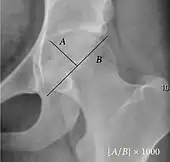

| Acetabular depth ratio | ![]() |

Deepness of acetabulum. | >250

|